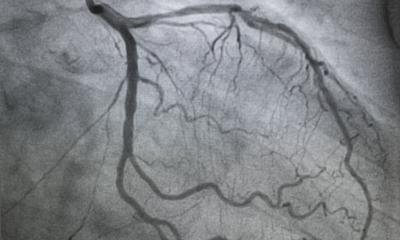

The basic prerequisite for CAS is an accurate model of the patient. To accomplish this, various image formats - whether it’s CT, MRI or PET/MRI scans- are prepared and combined with the help of software during the preoperative planning phase. Professor Markus Kleemann, Division Chief of Vascular and Endovascular Surgery at the University Medical Center Schleswig-Holstein, explains. “High-resolution data sets in the millimeter range can be reconstructed three-dimensionally. This image is subsequently transferred to the patient. The reconstruction conveys a more intuitive view of the findings, for instance, regarding the location of a tumor or vascular disease. Thanks to this visualization technique, today we have the chance to calculate distances, diameters or volumes prior to the intervention and accurately specify the surgical strategy.” The implementation during the surgery assumes that the information collected from the image data can be transferred to the surgical settings.

In some cases, a 3D model of the operable organ or bone is produced after the image reconstruction. In doing so, stents or implants can be positioned on a trial basis or accesses simulated to be able to operate as minimally invasively as possible. Based on these types of custom-made models, implants can also be custom-fit in some instances.